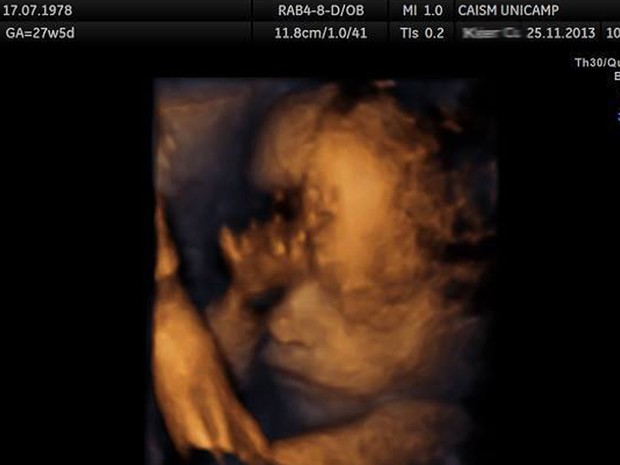

Exame de ultrassonografia realizado no Caism da Unicamp (Foto: Antonio Scarpinetti/Unicamp)Cesárea chama atenção